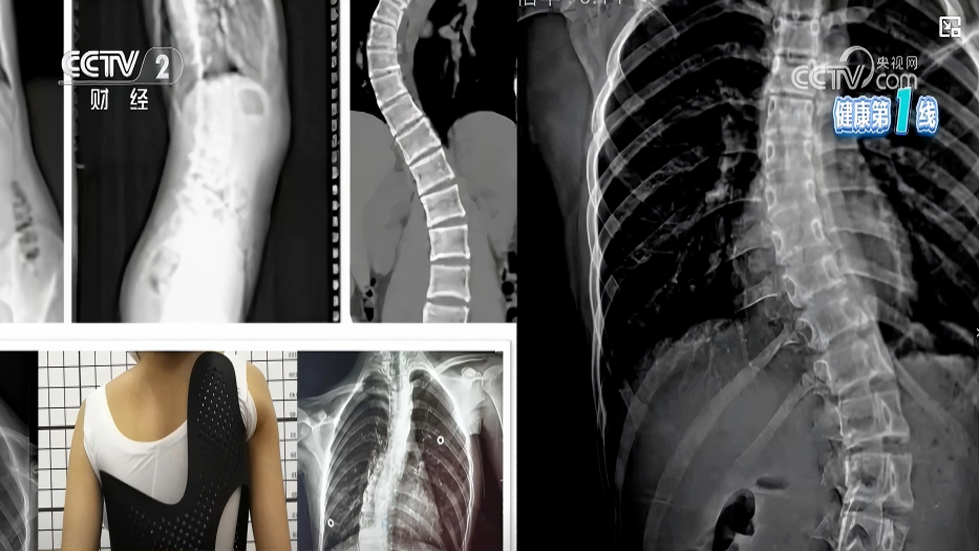

脊柱侧凸是一种复杂的脊柱三维畸形,国际脊柱侧凸研究学会(SRS)明确将其定义为:在站立位全脊柱冠状面X线片测量Cobb角≥10°。其中,特发性脊柱侧凸病因尚不明确,约占脊柱侧凸

脊柱侧凸是一种复杂的脊柱三维畸形,国际脊柱侧凸研究学会(SRS)明确将其定义为:在站立位全脊柱冠状面X线片测量Cobb角≥10°。其中,特发性脊柱侧凸病因尚不明确,约占脊柱侧凸发病率的80%,而青少年特发性脊柱侧凸(AIS)是最常见的类型,发生于10~18岁青少年群体。

AIS不仅会影响青少年的外观体态,还可能引发腰背疼痛、心理障碍,严重时会导致呼吸困难、活动能力受限,针对学生报考特殊专业可以会受限,给家庭和社会带来沉重负担。同时,青少年不良姿势体态与AIS密切相关,也容易引发家长和青少年的焦虑情绪。根据国际脊柱侧凸矫形与康复治疗学会(SOSORT)和SRS的专业意见,AIS的康复需要规范化评估与科学干预,其中非手术保守治疗是多数患者的核心干预选择。

对于未达到手术指征(通常Cobb角<45°,或骨骼未闭合、侧弯进展缓慢)的脊柱侧弯患者,保守治疗是控制病情进展、改善体态的关键手段。我国目前针对脊柱侧弯的非手术治疗方法多样,专业医疗机构的专科医生会根据患者的年龄、侧弯类型、Cobb角大小、骨骼发育情况等,选择合适的治疗方法或组合方案,以下为大家全面、专业解析各类保守治疗手段。

矫形支具是国际公认的控制脊柱侧弯进展最有效的非手术手段之一,适用于Cobb角超过20°且进行性加重风险较大的中重度脊柱侧弯患者,可单独应用,若同时配合专项康复训练,矫正效果会更佳。根据材质、矫正原理的不同,临床常用支具分为硬支具和软支具两类。

硬支具为传统刚性支具(如波士顿支具、色努支具),采用刚性材料量身定制,通过冠状面三点力、局部力对系统和矢状面平衡,限制脊柱异常弯曲和旋转,强制引导脊柱保持正确力线;

软支具为新型弹性支具,基于动态三维三点力生物力学原理,通过柔和精准的推压力启动神经肌肉调控,引导身体主动保持正确姿态,舒适度更高,适用于轻度侧弯或作为中度侧弯的辅助矫正。

支具治疗对患者依从性要求较高,硬支具通常需每天佩戴16-23小时,软支具通常需每天佩戴8-11个小时,定期复查并调整支具规格,才能确保矫正效果。